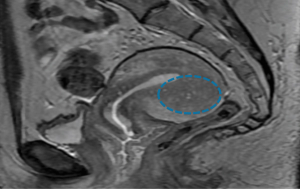

Comorbidities such as endometriosis can confound the picture in patients with adenomyosis, a condition that may lead to poor IVF outcomes.